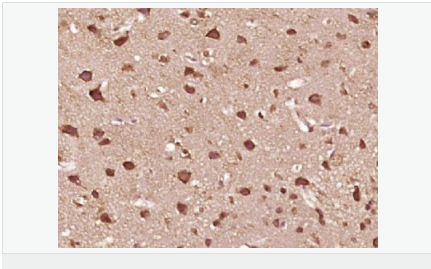

| 產(chǎn)品應(yīng)用 | WB=1:500-2000 ELISA=1:5000-10000 IHC-P=1:100-500 IHC-F=1:100-500 ICC=1:100-500 IF=1:100-500 (石蠟切片需做抗原修復(fù)) not yet tested in other applications. optimal dilutions/concentrations should be determined by the end user. |

| 產(chǎn)品介紹 | The protein encoded by this gene is a regulator of apoptosis and is structurally similar to caspase-8. However, the encoded protein lacks caspase activity and appears to be itself cleaved into two peptides by caspase-8. Several transcript variants encoding different isoforms have been found for this gene, and partial evidence for several more variants exists. [provided by RefSeq, Feb 2011] Function: Apoptosis regulator protein which may function as a crucial link between cell survival and cell death pathways in mammalian cells. Acts as an inhibitor of TNFRSF6 mediated apoptosis. A proteolytic fragment (p43) is likely retained in the death-inducing signaling complex (DISC) thereby blocking further recruitment and processing of caspase-8 at the complex. Full length and shorter isoforms have been shown either to induce apoptosis or to reduce TNFRSF-triggered apoptosis. Lacks enzymatic (caspase) activity. Tissue Specificity: Widely expressed. Higher expression in skeletal muscle, pancreas, heart, kidney, placenta, and peripheral blood leukocytes. Also detected in diverse cell lines. Isoform 8 is predominantly expressed in testis and skeletal muscle. Post-translational modifications: Proteolytically processed; probably by caspase-8. Processing likely occurs at the DISC and generates subunit p43 and p12. Similarity: Belongs to the peptidase C14A family. Contains 2 DED (death effector) domains. SWISS: O15519 Gene ID: 8837 Database links: Entrez Gene: 8837 Human Entrez Gene: 12633 Mouse Omim: 603599 Human SwissProt: O15519 Human SwissProt: O35732 Mouse Unigene: 390736 Human Unigene: 336848 Mouse Important Note: This product as supplied is intended for research use only, not for use in human, therapeutic or diagnostic applications. |